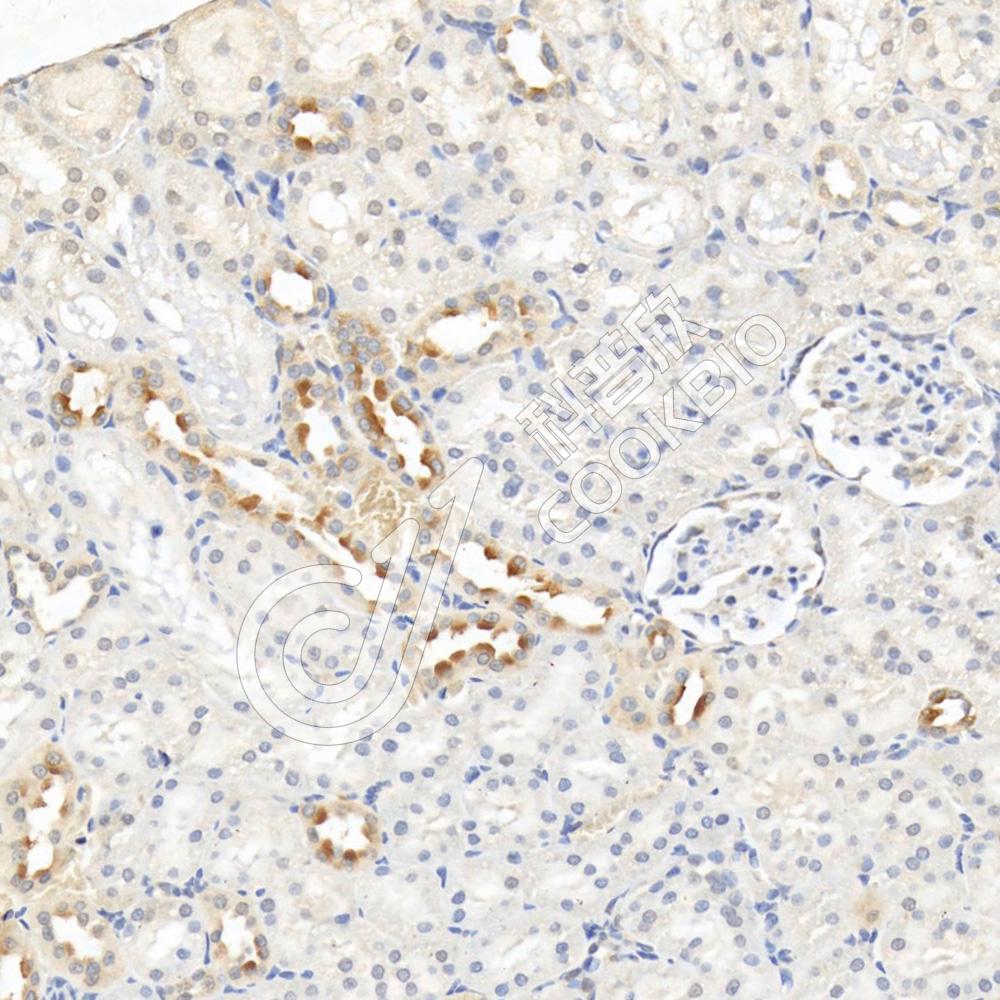

IHC检测GLS2蛋白(货号 K1335058).

样品: 小鼠肾, 4%多聚甲醛 (货号KSG1101) 固定12-24小时.

抗原修复: 柠檬酸抗原修复液(干粉, pH 6.0) (KSG1201), 98℃, 20分钟.

—抗: 1: 2100稀释, 4℃ 孵育过夜.

二抗: S-vision免疫组化多聚二抗(山羊抗兔),即用型 (货号KB3906), 室温孵育20分钟.

样品: 大鼠肾, 4%多聚甲醛 (货号KSG1101) 固定12-24小时.